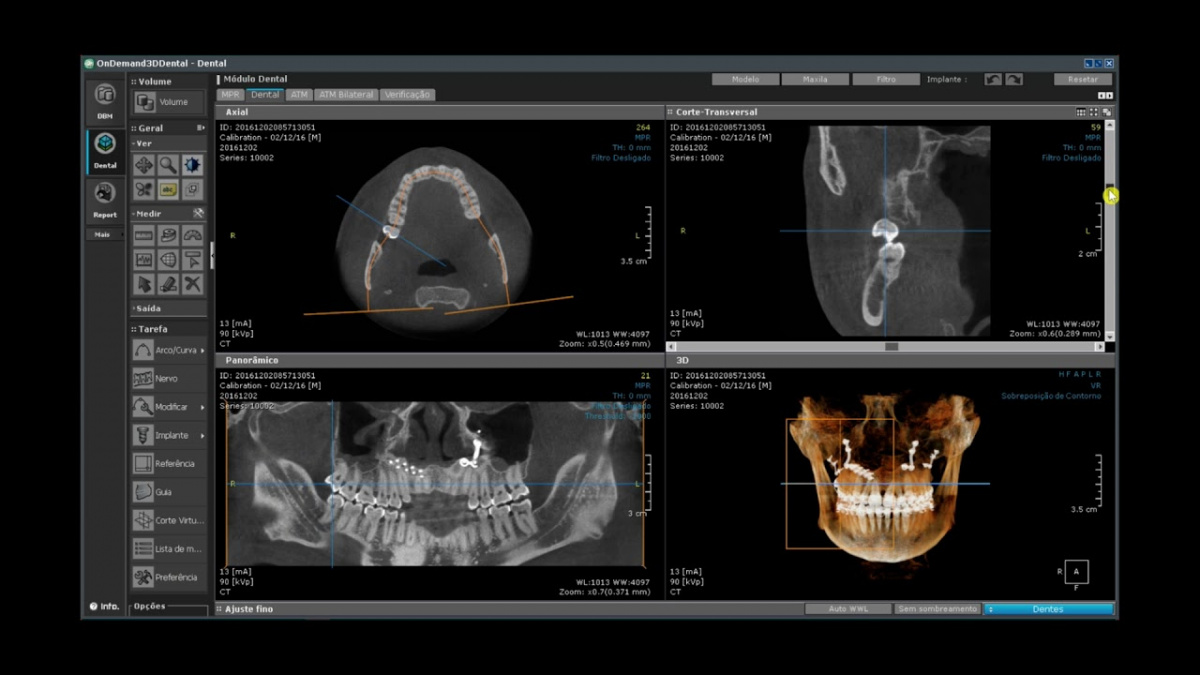

Немаловажным, а может главным вопросом, является универсальность программы-просмотровщика, в которой будут работать врачи-стоматологи. У Papaya 3D есть два варианта программ: Triana и OnDemand3D. Оба просмотровщика обладают схожим интерфейсом и имеют самые важные опции, а именно:

Triana.jpg  OnDemand3D.jpg

• режим MPR (многоплоскостная реконструкция). Именно здесь выстраивается интересующий участок челюсти или зуба для анализа.

• панорамный реформат. Возможность постройки классической и сегментарной панорамы позволяет продемонстрировать план лечения пациенту, а также оценить расположение анатомических структур на боковых кросс-секциях.

• модуль дентальной имплантации. Возможность виртуальной установки дентального имплантата с анализом окружающей костной ткани. В библиотеке представлен широкий спектр имплантологических систем с индивидуальной прорисовкой имплантата.

• выделение нижнечелюстного канала позволяет продемонстрировать расположение важного анатомического образования и определить зону безопасности при проведении лечения.

• функции плотности, линейных измерений и угла – необходимы для получения полноценной информации для последующего лечения.

• 3D режим – показывает трехмерную модель челюсти с целью определения аномалий, деформация, а также визуализации виртуальных имплантатов.

triana3.jpg triana4.jpg triana5.jpg

OnDemand3D (1).jpg OnDemand3D (2).jpg OnDemand3D 1.jpg

Таким образом обе программы являются простыми в пользовании, но обладающими обширным спектром возможностей для диагностики любыми специалистами-стоматологами. В данные программы происходит загрузка классических файлов DICOM 3.0, которые являются общепринятым форматом записи данных пациента. Это важный момент, так как позволяют врачу, имеющему полную версию программы загружать даже сторонние исследования и просматривать их в этих программах. Простота в освоении этих программ позволяет даже специалисту, не работающему раннее с этими программами, быстро адаптироваться и получить качественную информацию. Возможность выгрузки STL-файла дополнительно создает возможность интегрировать данные с цифровым ортопедическим протоколом.